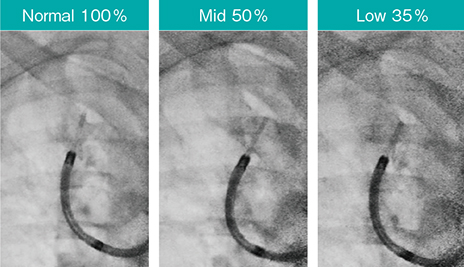

3.透視パルスレートと透視線量モード

Ultimax-iは、ダイヤルを回すだけで透視パルスレートを1.0~15fpsまで調整可能で、例えばoctave SPに加え透視パルスレートを7.5fpsに設定することで、従来よりも約82.5%の被ばく低減(従来の17.5%の線量)が実現する。さらに、透視線量モードをNormalモード(標準の線量)、Midモード(標準の50%の線量)、Lowモード(標準の35%の線量)の3段階から透視を切らずにワンタッチで選択できる(図10)。画質は大きく変わらないため、ルート確認後はNormalモードからMidモードにするなど、透視パルスレートと同様に細やかな使い分けが可能である(図11)。

図11 透視線量モードによる画質の比較

Accent適用、スコープ:BF-P290、ガイドシース:SG-400C(オリンパス社製)